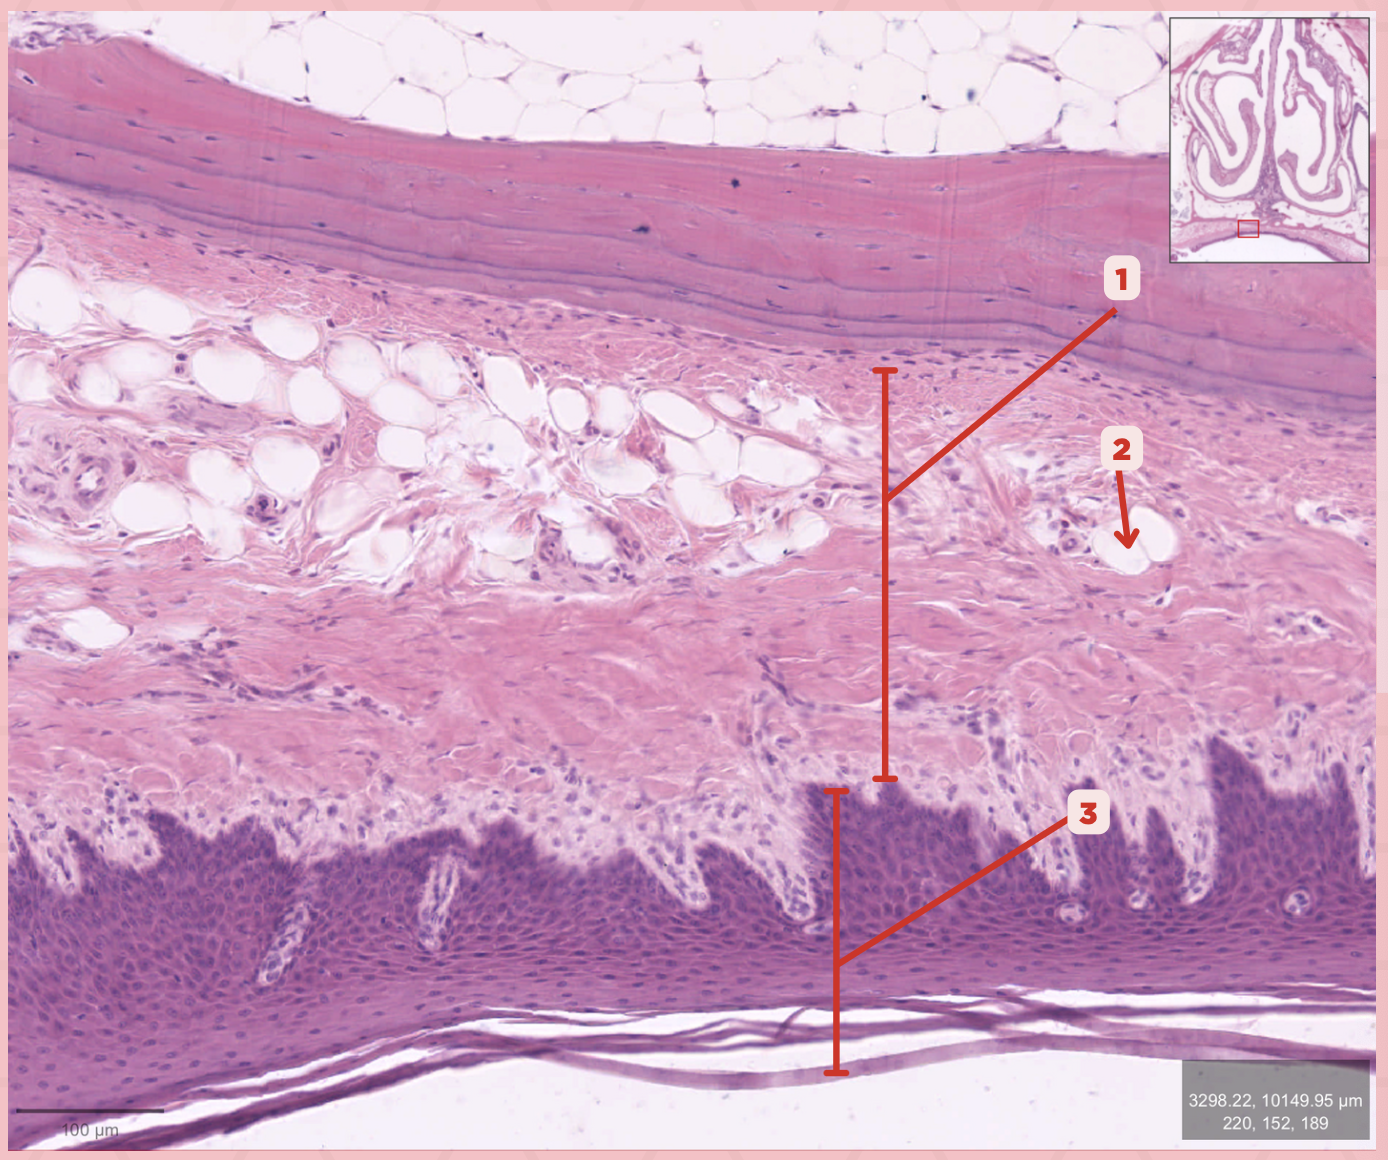

Lamina Propria

Identify the structure labeled as 1.

Adipocytes

Identify the structure labeled as 2.

Keratinized stratified squamous epithelium

Identify the structure labeled as 3.

Mucosa

Identify the structure labeled as 1.

Submucosa

Identify the structure labeled as 2.

Mucous gland

Identify the structure labeled as 3.

Serous gland

Identify the structure labeled as 4.

Loose connective tissue

What type of connective tissue comprise no. 3?

Adipocytes

Together with blood vessels and nerves, these cells are abundant in no. 3.